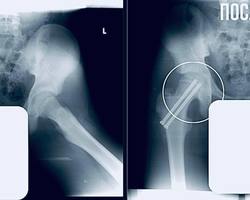

В ходе обследования выяснилось, что у подростка – юношеский эпифизеолиз.

Патология подразумевает смещение головки бедренной кости, характерное для периода активного роста скелета.

— Пациенту требовалась срочная операция. Мы выполнили фиксацию сустава, чтобы остановить смещение и дать ему возможность правильно развиваться. Это убережет юношу от раннего артроза и ограничений подвижности в будущем, — отметил главный врач МОДКТОБ Александр Григорьев.